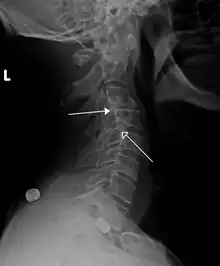

| Grade 1 retrolistheses of C3 on C4 and C4 on C5 | |

A retrolisthesis is a posterior displacement of one vertebral body with respect to the subjacent vertebra to a degree less than a luxation (dislocation). Retrolistheses are most easily diagnosed on lateral x-ray views of the spine. Views where care has been taken to expose for a true lateral view without any rotation offer the best diagnostic quality.

Retrolistheses are found most prominently in the cervical spine and lumbar region but can also be seen in the thoracic area.